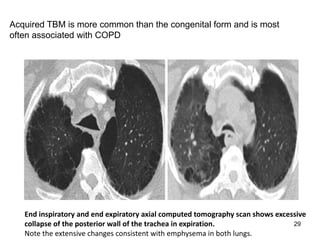

Acquired TBM is more common than the congenital form and is most

often associated with COPD

End inspiratory and end expiratory axial computed tomography scan shows excessive

collapse of the posterior wall of the trachea in expiration.

Note the extensive changes consistent with emphysema in both lungs.